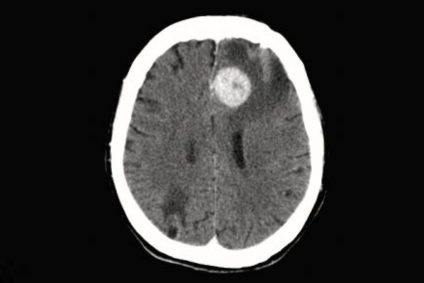

que es un linfoma cerebral

Muñoz, N. et al. (2017). El linfoma primario del sistema nervioso central (LPSNC) es una enfermedad poco frecuente y agresiva. [Fotografía]. Recuperado de www.elsevier.es

En los últimos años, la investigación sobre el linfoma cerebral primario ha dado lugar a nuevos enfoques terapéuticos. Por ejemplo, los inhibidores de la tirosina quinasa de Bruton, como el ibrutinib, han mostrado una amplia eficacia. Además, la inmunoterapia con agentes como el lenalidomida está siendo evaluada en ensayos clínicos, ofreciendo esperanza para aquellos con formas más agresivas de la enfermedad.

Estos avances destacan la importancia de un enfoque multidisciplinario en el manejo del linfoma cerebral. Se destaca, así, la necesidad de especialistas en neurología, oncología y radiología, así como también el hecho de que trabajen en conjunto, con el fin de optimizar los resultados del tratamiento.

Como ya adelantamos previamente, el linfoma cerebral se diagnostica mediante resonancia magnética con gadolinio y, en casos específicos, análisis de líquido cefalorraquídeo para detectar células malignas. Su tratamiento se basa en quimioterapia de altas dosis con metotrexato, complementada con radioterapia o trasplante autólogo de células madre, aunque las recaídas son frecuentes.